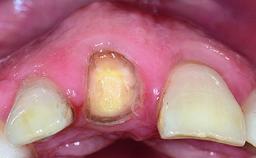

Replacement of an Ankylosed Central Incisor with a Gingival Recession: Tooth Extraction with Socket Grafting and Late Implant Placement with Simultaneous Contour Augmentation

In 2008, a healthy 15-year-old female, non-smoking patient presented at our clinic with a major esthetic problem of tooth 21. Her dental history revealed that the tooth had been avulsed by trauma years before. As a result, the replanted and temporarily splinted tooth had ankylosed and was in severe apical malposition. The ankylosed tooth exhibited a significant gingival recession that disturbed the patient greatly. Due to the patient’s low age and with her skeletal growth not completed, periodic follow-up visits were scheduled to monitor the situation until the patient was old enough for implant therapy.